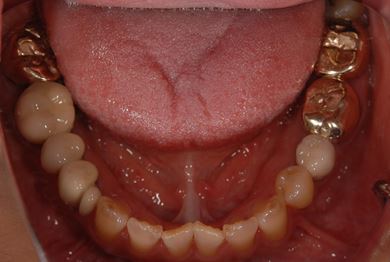

治療前

• 治療前